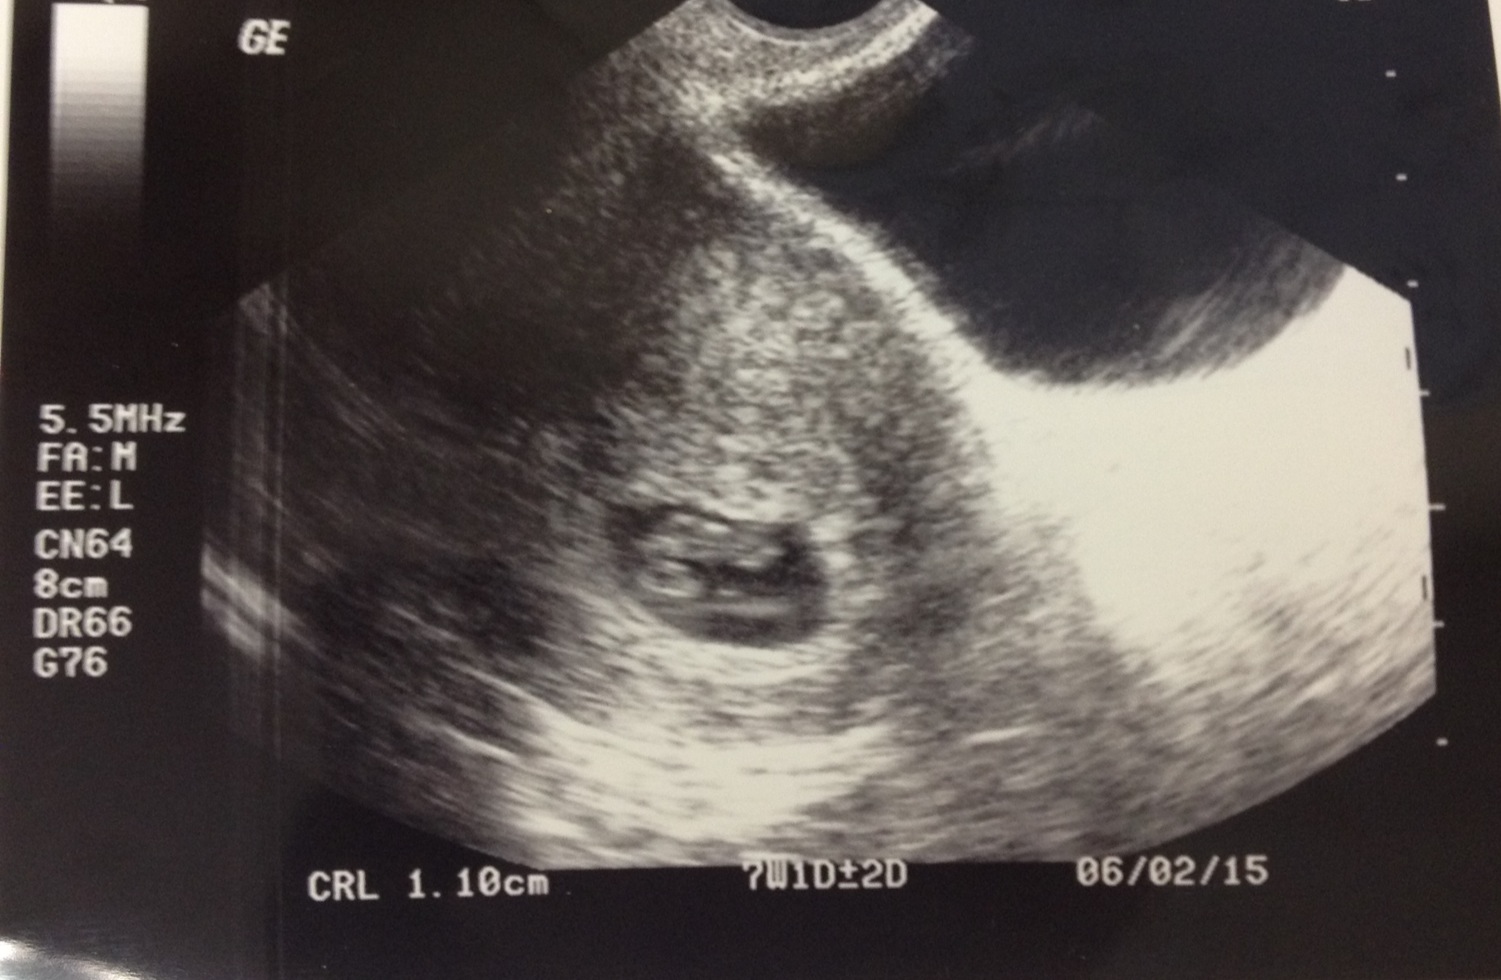

• Had my first US yesterday!!  Measured exactly at 7w which was what I calculated from my LMP.

Saw the little bean, heard and saw the heartbeat.. it was amazing!!!!  It I so much more real now (especially for DH.. it's so cute to see him amazed by this).

The tech said the heart rate was 175 or maybe she said 165 I could hardly focus on what she was saying.  Is that too high??  From what I've read, 7w heart rates are more around 120-140...but I know absolutely nothing about this stuff.